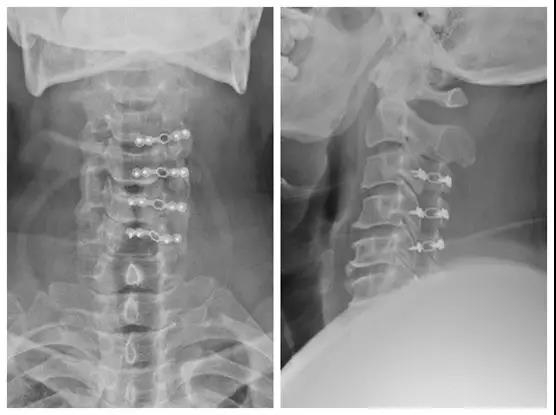

术后X线正侧位

点击此处查看手术视频讲解